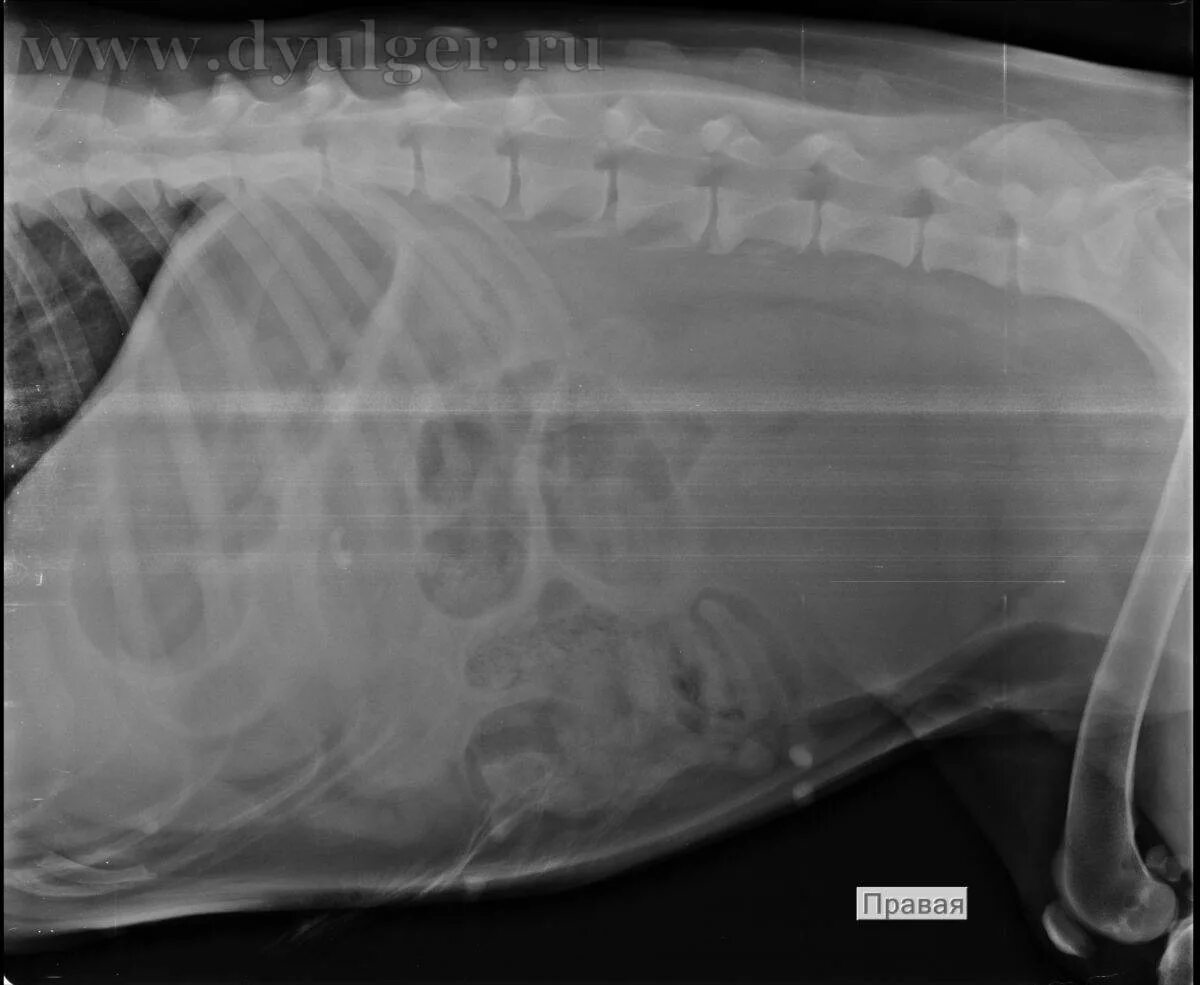

Лимфома у собак симптомы